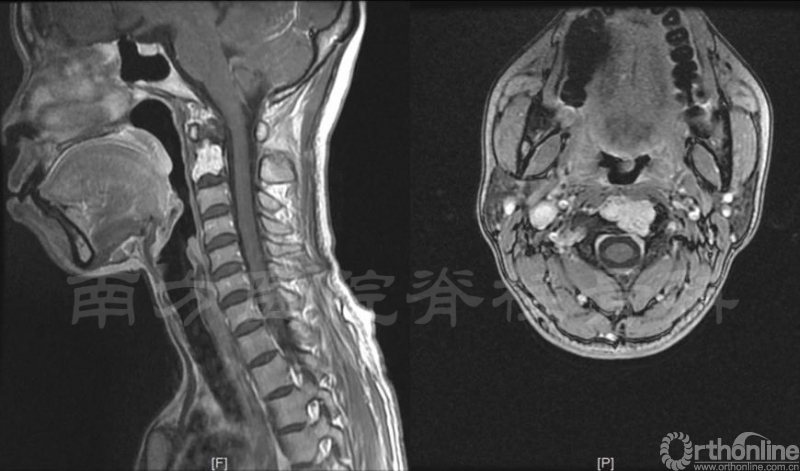

术前MRI示肿瘤侵犯枢椎大部分椎体